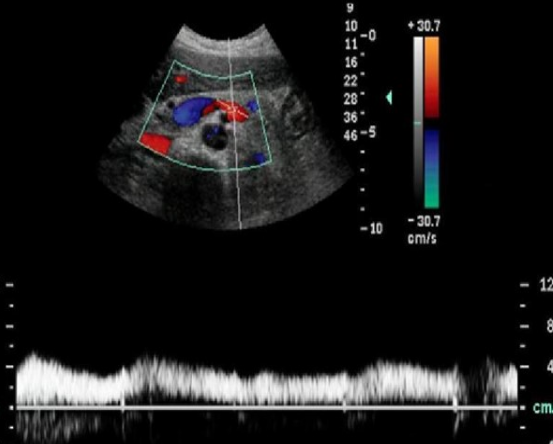

Identify this image.

Splenic aneurysm